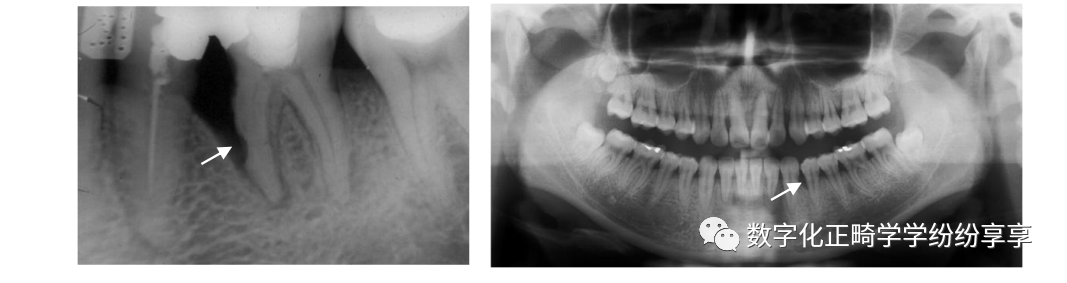

根尖周疾病 periapical disease:

根尖周脓肿

曲面断层片怎么看正畸【曲面断层片(全景片)】如何解读和查看:牙周?牙体?牙髓?关节?_https://www.jmylbn.com_新闻资讯_第7张

随病情发展可见病原牙为中心、骨质破坏较重、弥散性破坏、边界不清的投射区。骨硬板消失,病变一般较局限,外周可有骨质增生反应。越靠近患牙破坏越严重,密度越低

根尖周肉芽肿

曲面断层片怎么看正畸【曲面断层片(全景片)】如何解读和查看:牙周?牙体?牙髓?关节?_https://www.jmylbn.com_新闻资讯_第8张

在病原牙根尖根侧方或根分叉有圆形或卵圆形的密度减低区,病变范围较小,直径一般不超过 1cm,周界清楚,无质密骨硬板,病变周围骨质正常或稍变致密。

根尖周囊肿

曲面断层片怎么看正畸【曲面断层片(全景片)】如何解读和查看:牙周?牙体?牙髓?关节?_https://www.jmylbn.com_新闻资讯_第9张

曲面断层片怎么看正畸【曲面断层片(全景片)】如何解读和查看:牙周?牙体?牙髓?关节?_https://www.jmylbn.com_新闻资讯_第10张

以病原牙尖为中心形成大小不等的圆形或卵圆形、骨质破坏低密度病变区,密度均匀。边缘清晰锐利,周围骨质长期受刺激而在囊肿边缘有致密线条影。可致骨膨隆。